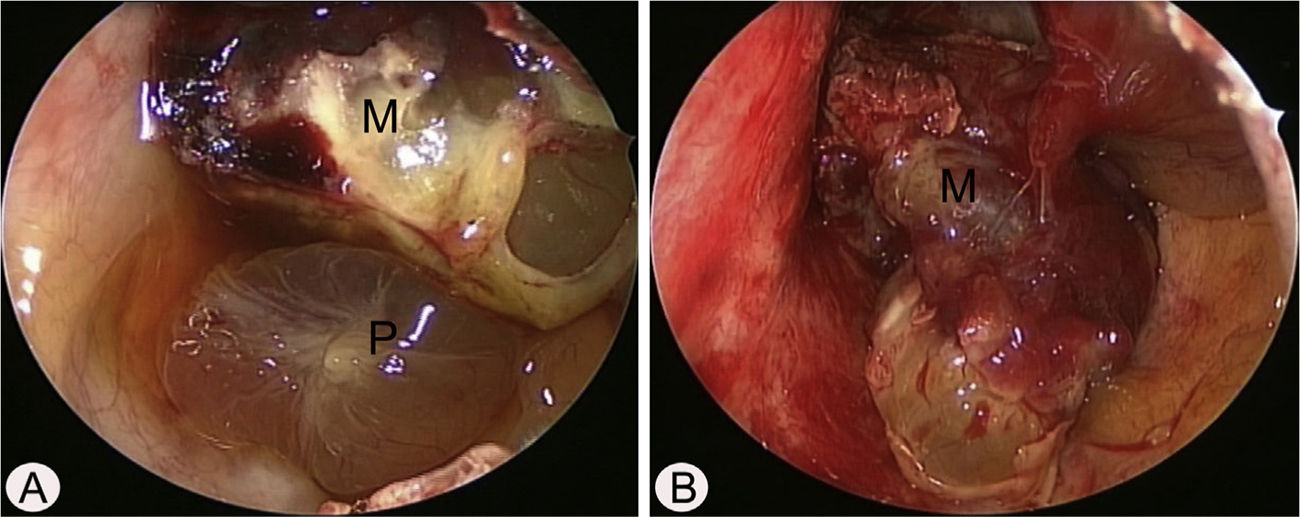

Case reportA 17-year-old male was referred to our outpatient clinic because of recurrent epistaxis after left nasal polypectomy. He had undergone nasal polypectomy due to nasal congestion at a local clinic 10 days ago. He had neither other symptoms nor any medical history. There was no history of trauma and no sign of allergy. The endoscopic examination revealed bulging of lateral nasal wall and bleeding due to left maxillary sinus mass (Fig. 1A). A Computed Tomography (CT) scan of the paranasal sinuses showed heterogenous enhancing mass in left maxillary sinus without adjacent bony involvement (Fig. 1B and C). On Magnetic Resonance Imaging (MRI), the mass expanding left maxillary sinus had mixed high signal intensity on T1-weighted images (T1WIs) and heterogenous high signal intensity on T2-weighted images (T2WIs) with an avid enhancement (Fig. 1D–F). Considering the location of tumor, surgical access was gained via Caldwell-Luc approach under general anesthesia because transnasal endoscopic sinus surgery had high risk of bleeding. The mass was originated from medial wall and partial superior wall of left maxillary sinus (Fig. 2A and B). The base of the lesion including the healthy mucosa around it was successfully removed with harmonic scalpel and microdebrider under direct visualization using a nasal endoscope and cauterized using suction cautery for prevention of recurrence (Fig. 3A). Histopathologic examination showed variable sized and irregular shaped vascular spaces with thrombus, consistent with arteriovenous malformation (Fig. 3B). Postoperative course was uneventful and he was discharged five days after surgery. Endoscopic examinations and CT performed 3 months postoperatively showed no evidence of recurrence.

Intraoperative endoscopic findings via Caldwell-Luc approach. (A) The polypoid mucosa (P) was detected in the inferior portion of left maxillary sinus. (B) After removal of polypoid mucosa, highly vascular mass (M) was originated from the medial and partial superior wall of left maxillary sinus.